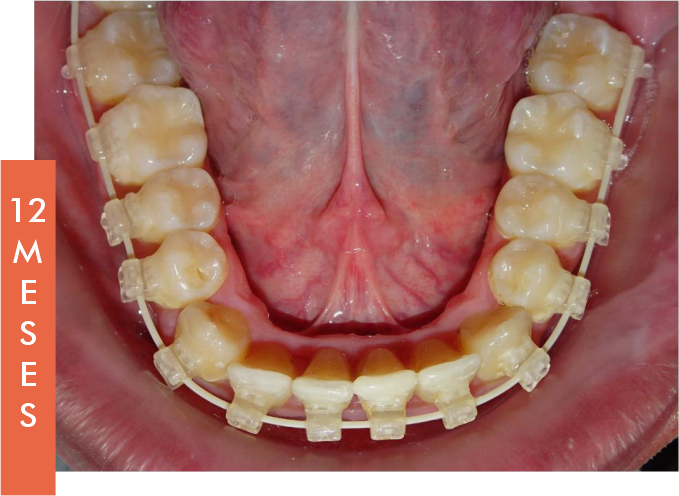

La BTM permite restaurar el Arco Natural Dentoalveolar, mejorando notablemente la estética dental y facial del paciente. Esta filosofía busca devolver una oclusión funcional y estable, respetando la anatomía natural.

Los segundos molares superiores, clave en esta técnica, se mantienen protegidos de fuerzas externas, sirviendo como punto de referencia para lograr una expansión transversal eficaz y controlada.

Esto convierte a la BTM en una herramienta esencial para tratamientos que respetan la biología del paciente.

- Tratamientos más rápidos y seguros.

- Reducción del tiempo de tratamiento y número de visitas.

- Mejora en la estética facial y funcionalidad oral.

- Aplicación de fuerzas ortodóncicas que respetan la fisiología del paciente. Fuerza aplicable de arcos de 20g.